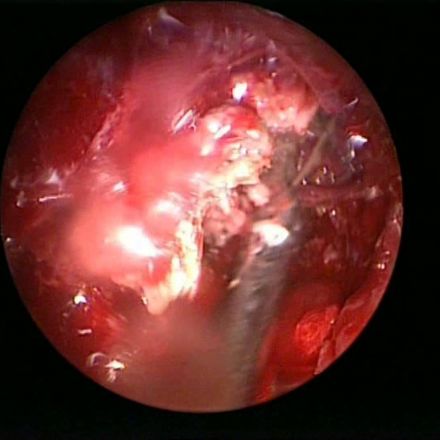

Chronic Fungal Sinusitis